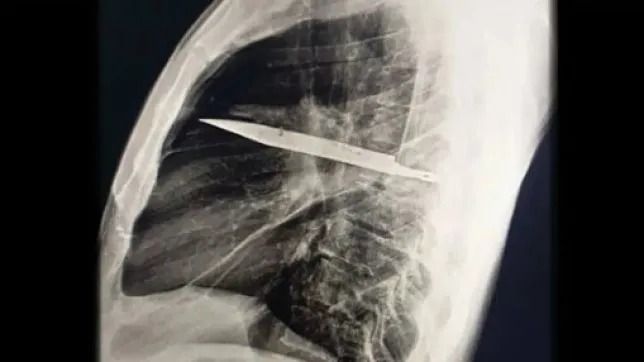

Homem descobre que vivia há 8 anos com uma faca alojada no peito